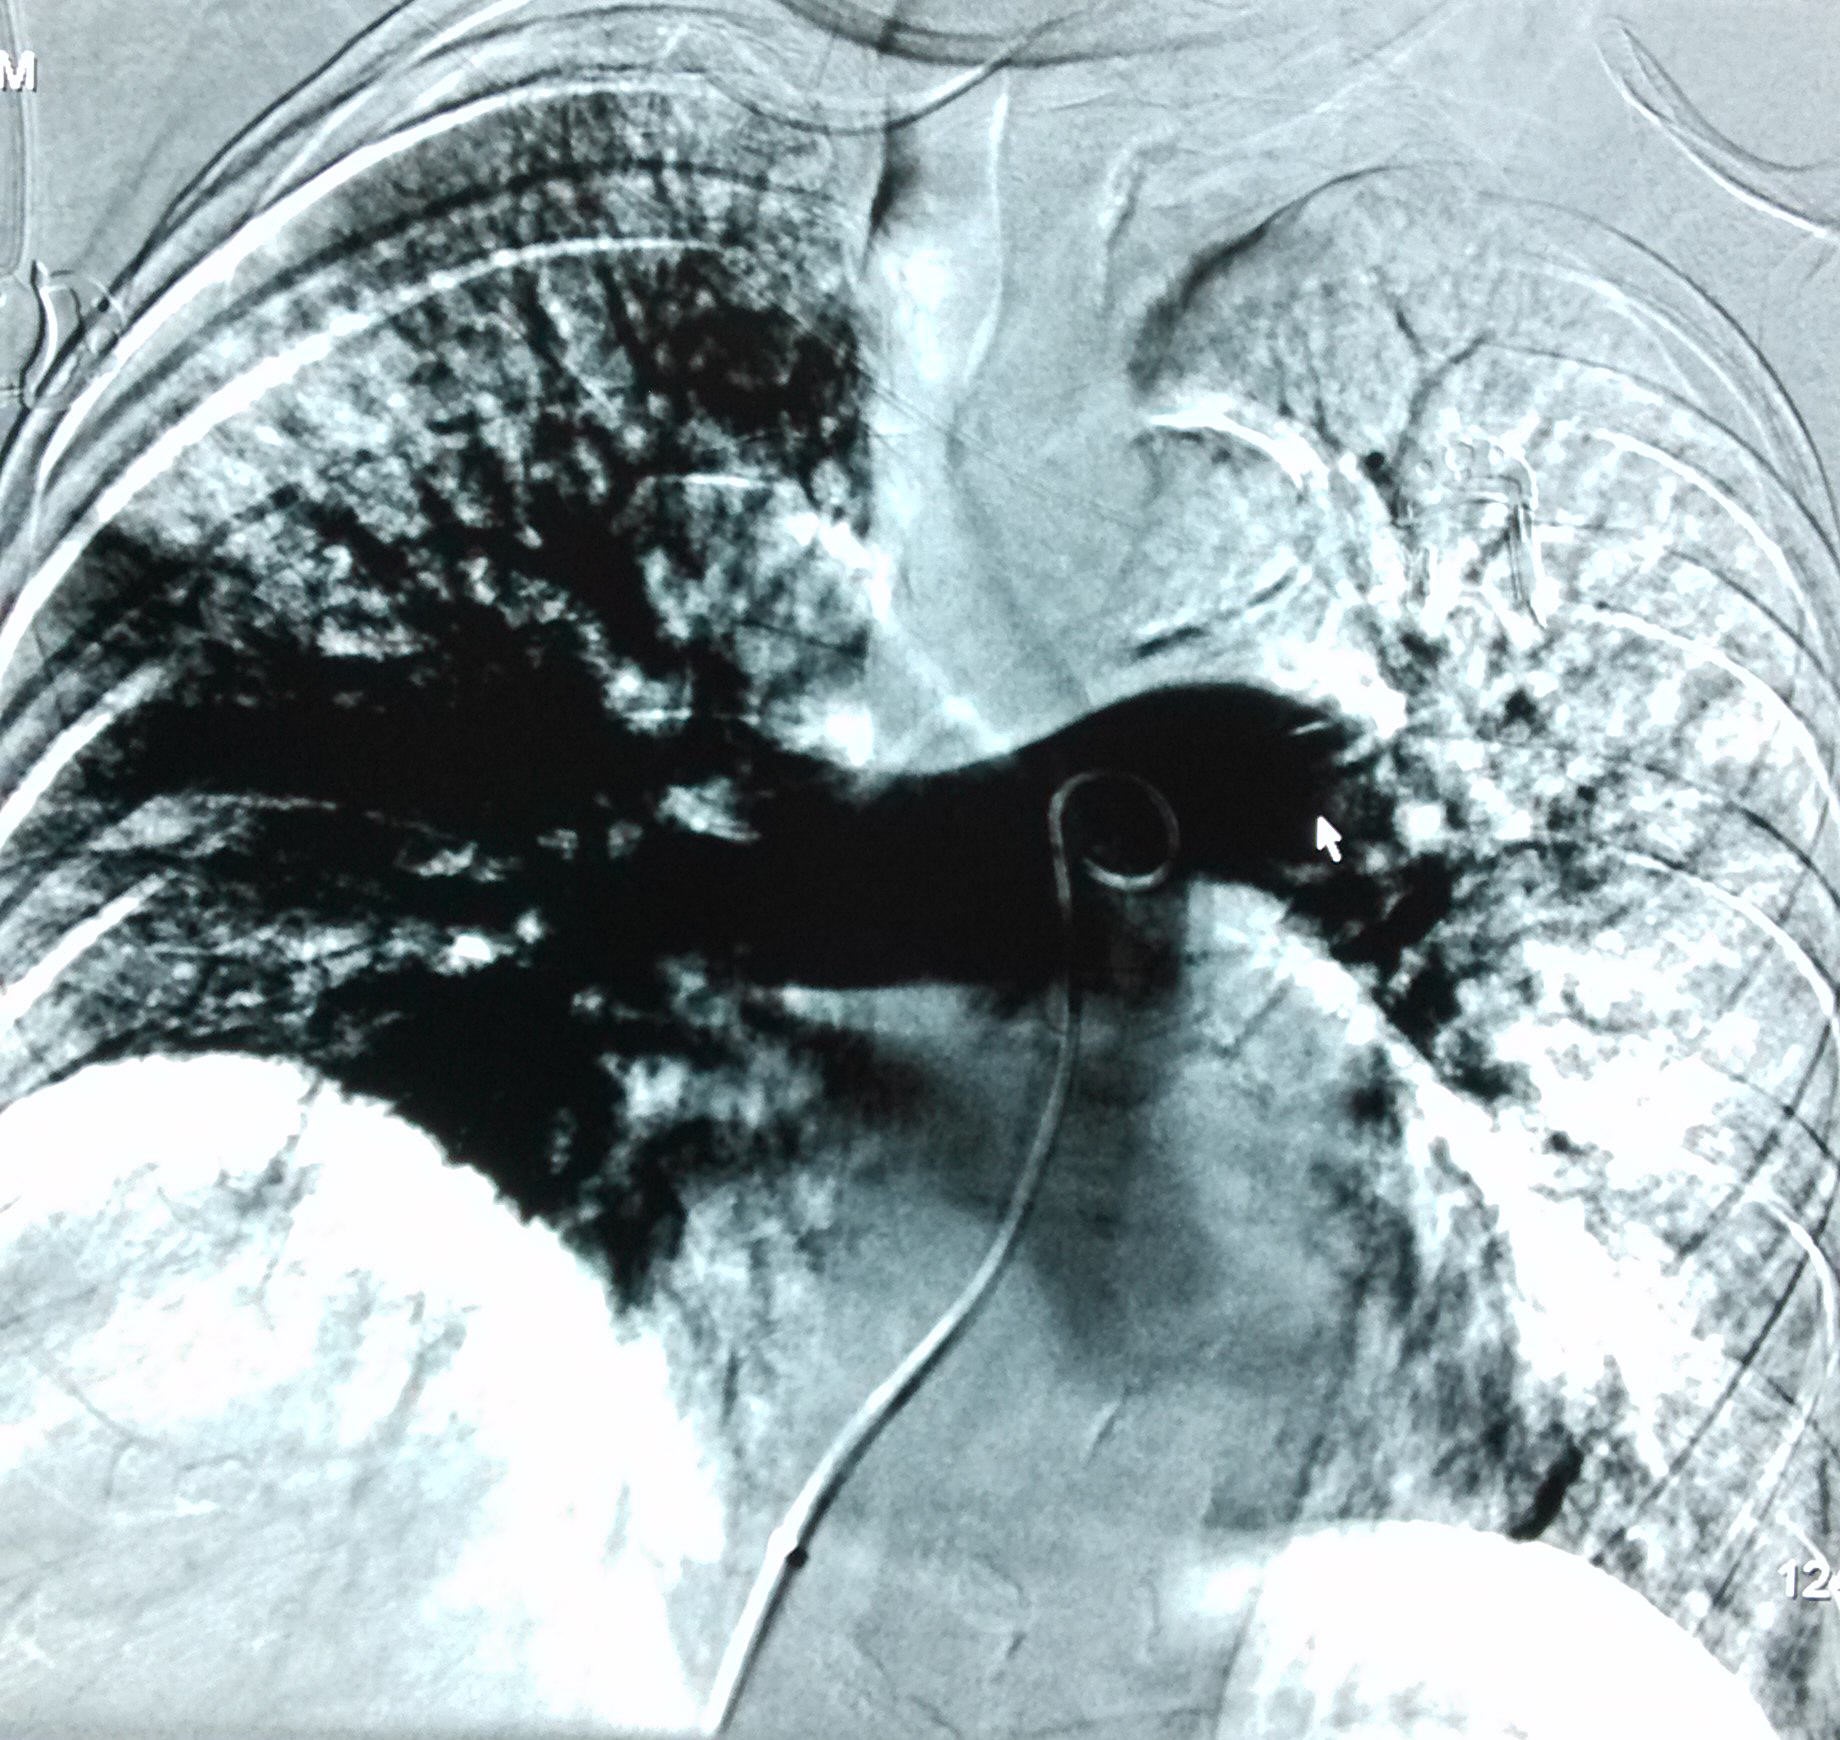

我在手术室门外等着,非常安静。我想手术室里面肯定是紧张忙碌,如履薄冰。这只有医师自己体会,而我只能想像……终于,手术约在23:40分结束了。赵克强医生请我在术间看了造影影像和血栓的手术前后比较。我高兴的看到母亲很好,血栓通了!

(箭头示左肺主干堵塞位置)